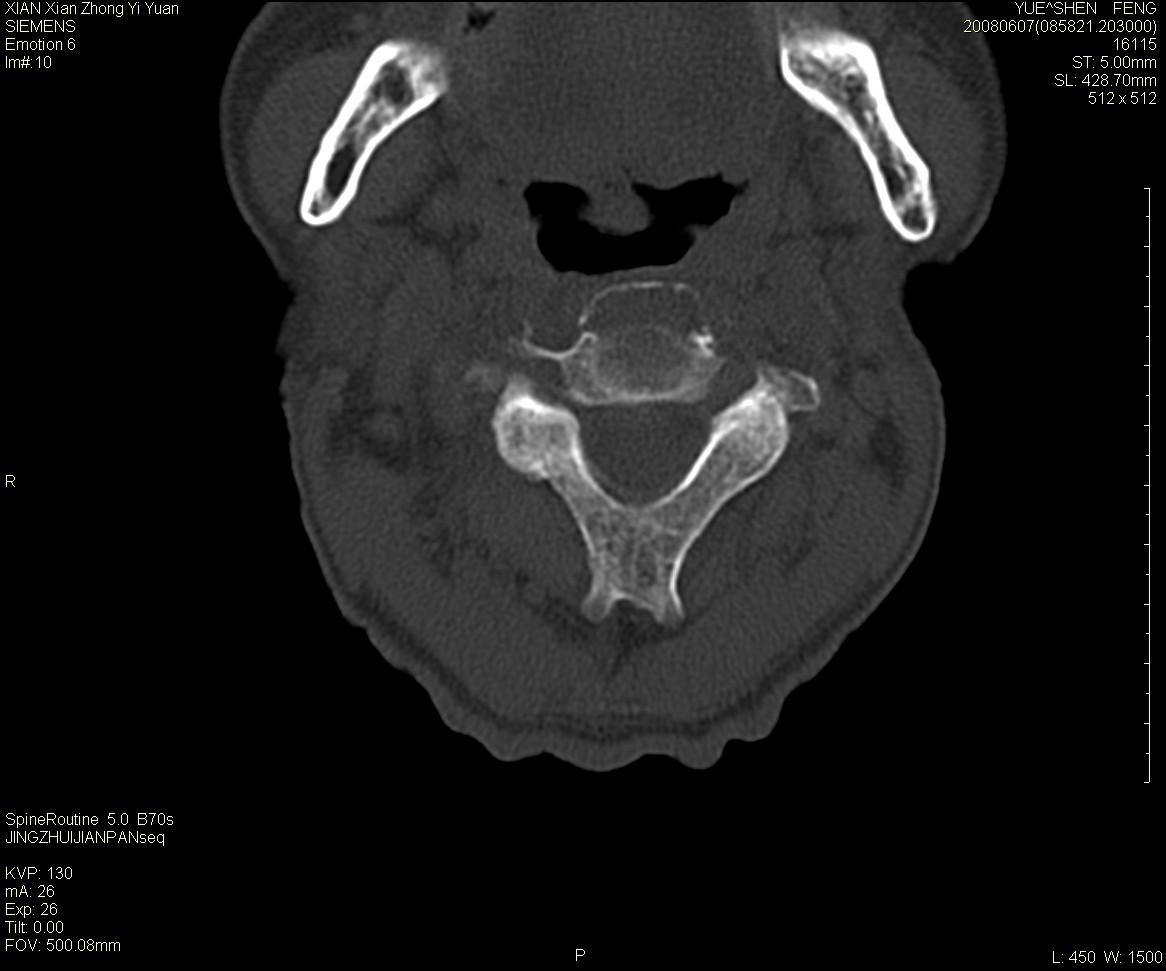

标题: CT13889:M72,颈部疼痛两年,近来加重。 [打印本页]

标题: CT13889:M72,颈部疼痛两年,近来加重。

作者: XIANXIANZHONGYI    时间: 2008-6-9 18:06

考虑浆细胞瘤

依据:

1 老年男性,颈部疼痛两年余。

2 ct:枢椎椎体显示膨胀性溶骨性骨质破坏,受损区域较大,边界清晰,其中似可见有小囊状结构,并残存有少量的骨小梁。病变与正常骨组织之间有一狭窄的分界区。受损部位部分边缘显示轻度骨质硬化。病灶突破骨皮质并在椎管形成软组织肿块影。

影像学检查:骨骼x线表现为单一部位的溶骨性改变,受损区域较大,边界清晰,其中可见有小囊状结构,少数可残存有少量的骨小梁。病变与正常骨组织之间有一狭窄的分界区。部分患者可见到病理性骨折,少数表现为受损部位的骨质硬化。ct和磁共振(mri)检查可以更加清晰地显示病损范围和性质以及周围软组织情况,并可能发现x线未显示的病灶以及更准确地判断骨髓是否受累。骨孤立性浆细胞瘤的ct和mri表现为扩张性溶骨性改变,骨质的破坏区完全被软组织肿块所代替,骨质膨胀,边界清晰,常突破骨皮质并在附近形成软组织肿块影。脊柱受累还可深入到锥管压迫神经束或神经根。